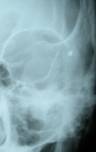

Radiological tests will be performed in order to detect possible foreign bodies present in deep tissue.

![]() |

| Bullet lodged in the upper orbit | |